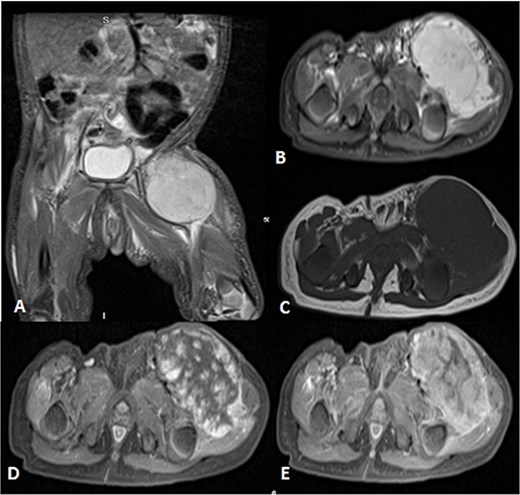

Pathology showed a round blue cell; thus, chest, abdomen and pelvis CT was done, which showed two solid pulmonary nodules and a 3.8 × 2.1 × 3.4 cm and incidental findings of neck mass involving the left sternocleidomastoid muscle. Further assessment was done by neckMRI, which shows a homogenously high-signal-intensity mass arising from the left sternocleidomastoid muscle on STIR with heterogeneous enhancement and an area of central necrosis on postcontrast images. However, during neck MRI protocoling a right cerebellar mass was identified and further images of the brain were obtained. The brain MRIs showed multiple scattered rounded lesions that showed high signal intensity at the gray–white matter junction seen at right frontoparietal lobes and in the right cerebellar hemisphere, findings in keeping with brain metastasis (Fig. 8). To treat the hydrocephalus, an external ventricular drain was implanted. Unfortunately, the patient passed away as a result of brainstem metastases as the disease worsened.

Patient underwent brain and neck MRI after incidental findings of left neck mass on chest CT. (A) Axial enhanced chest CT and the imaged part of the neck show a large heterogeneously enhanced left neck mass mostly arising from the left sternocleomastoid muscle with central necrosis causing mild mass effect upon left internal jugular vein with no sign of invasion or thrombosis. (B and C) Coronal STIR and postcontrast T1 fat-saturated images show homogenously high signal of the left neck mass arising from the left sternocleomastoid muscle on the STIR image with heterogeneous enhancement and central necrosis on the postcontrast image. (D and E) Axial T2WI images show multiple scattered, rounded high-signal-intensity supra- and infratentorial lesions at the gray–white matter junctions involving right frontoparietal lobes and the right cerebellar hemisphere, in keeping with brain metastasis.